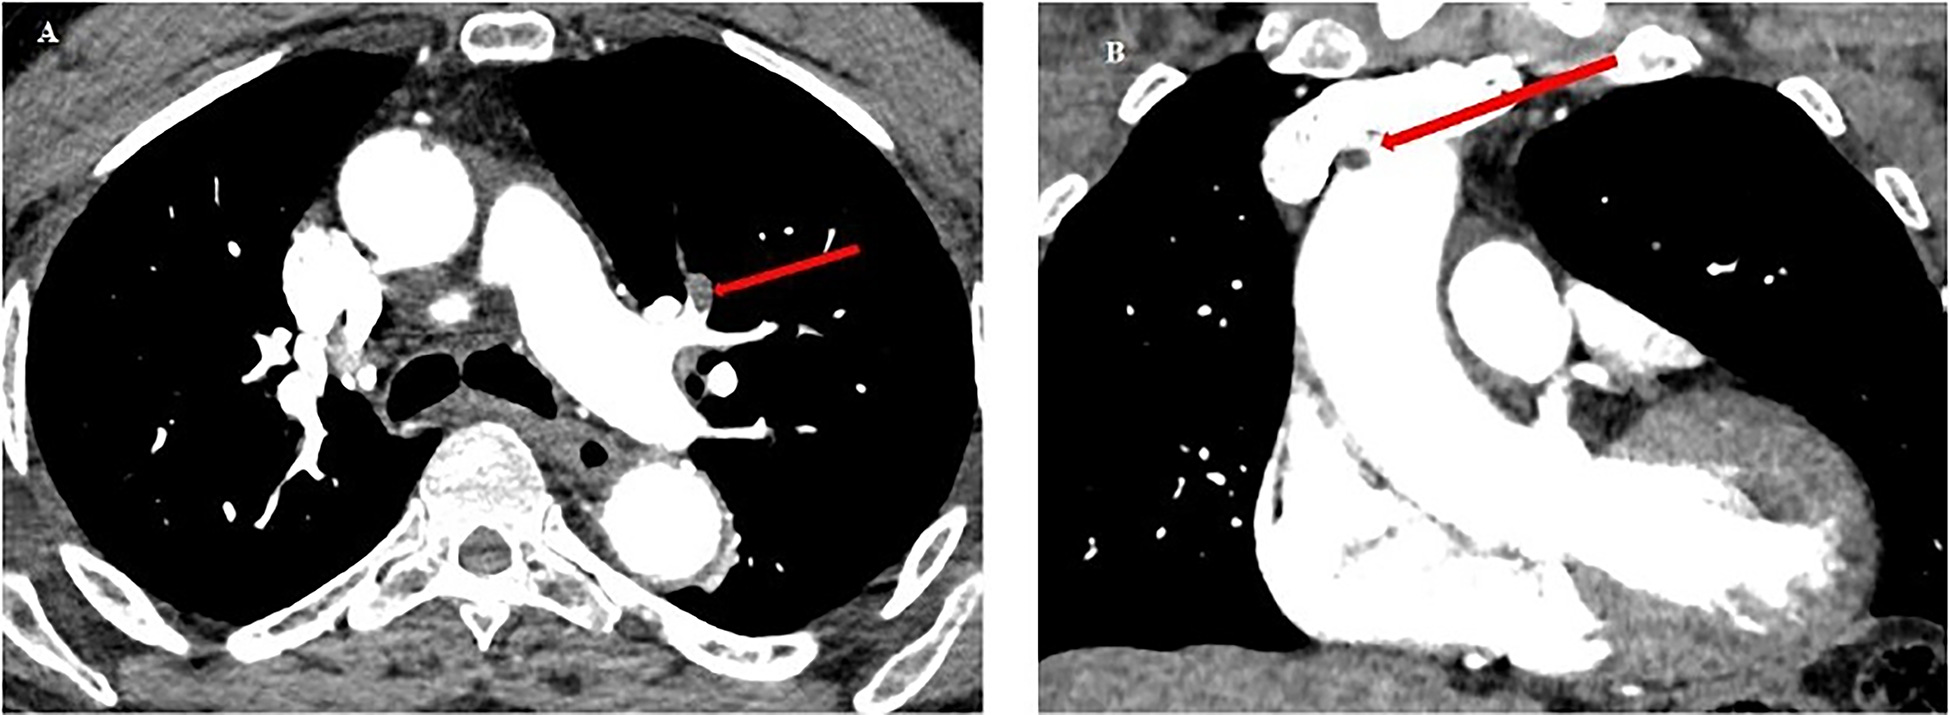

Figure 6

Chest CT scan from patient no.2. (A) Red arrow: pulmonary embolism of the upper lingular segment. (B) Red arrow: thrombus in the lumen of the ascending aorta (5 mm diameter), and of the aortic arch at the level of the birth of the brachiocephalic arterial trunk (6 mm).